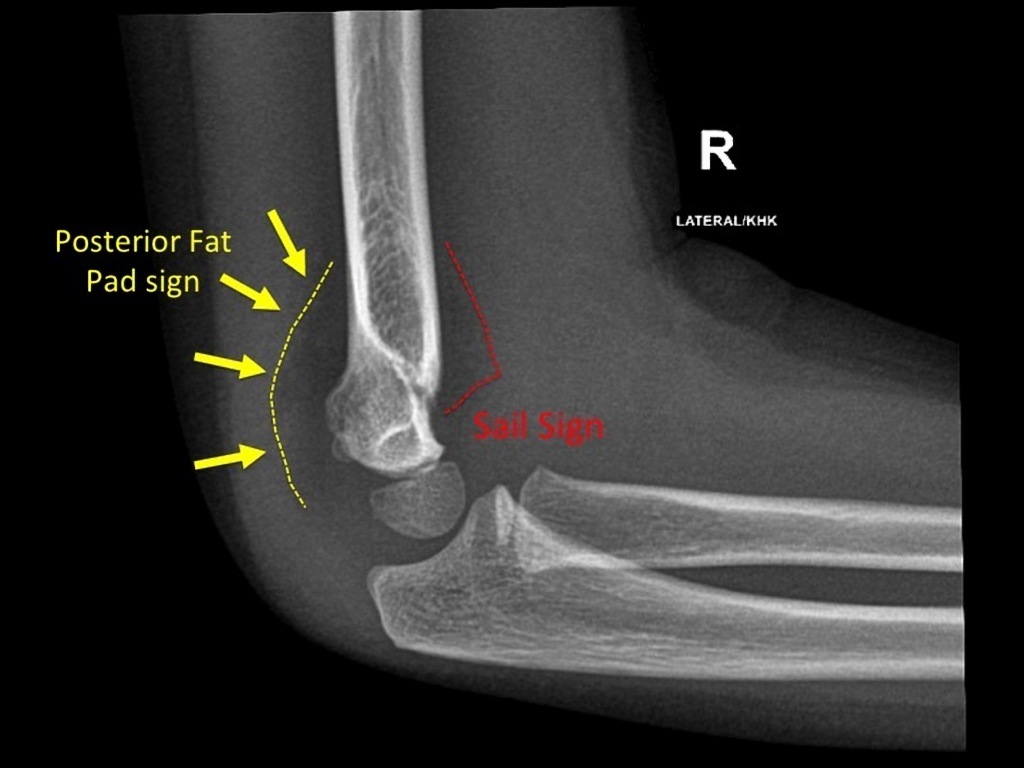

What is the posterior fat pad sign?

a lucent crescent of fat located in the olecranon fossa on a true lateral view of an elbow joint with the elbow flexed at a right angle

What does a posterior fat pad sign indicate? What should you look for in adults? In children?

Indicates an elbow joint effusion that suggests a non-displaced fracture

In adults: radial head fracture

In children: supracondylar fracture

What is the anterior fat pad sign?

The elevation fof the anterior fat pad to create a silhouette

What does an anterior fat pad sign indicate? What should you look for in adults? Children?

Joint effusion as anterior fat pad is elevated away from humerus –> intra-articular fracture